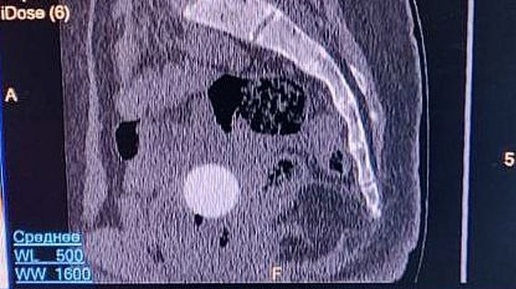

В Кировской областной детской клинической больнице произошел необычный медицинский случай. К нейрохирургу Эдуарду Сырчину привели 11-летнюю девочку, которая жаловалась на периодически возникающие боли в области копчика. Особенно сильно дискомфорт проявлялся при физической активности и смене положения тела. Со слов матери юной пациентки стало известно, что некоторое время назад девочка поскользнулась и упала, ударившись именно той областью, где теперь чувствовала боль. Однако изначально болезненные проявления были настолько незначительными, что родители не придали им особого значения...